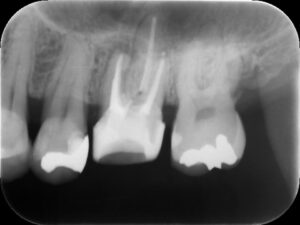

再根管治療後レントゲン。多少の違和感はあったものの、根管内部がきれいになり、排膿を認めないことから根管充填(薬を詰めること)を行った。根尖部までしっかりと薬が詰まっているのが分かる。歯根の内部がきれいな状態であれば、歯科医にはそれ以上出来ることはない。悪戯に弄り過ぎてはいけない。